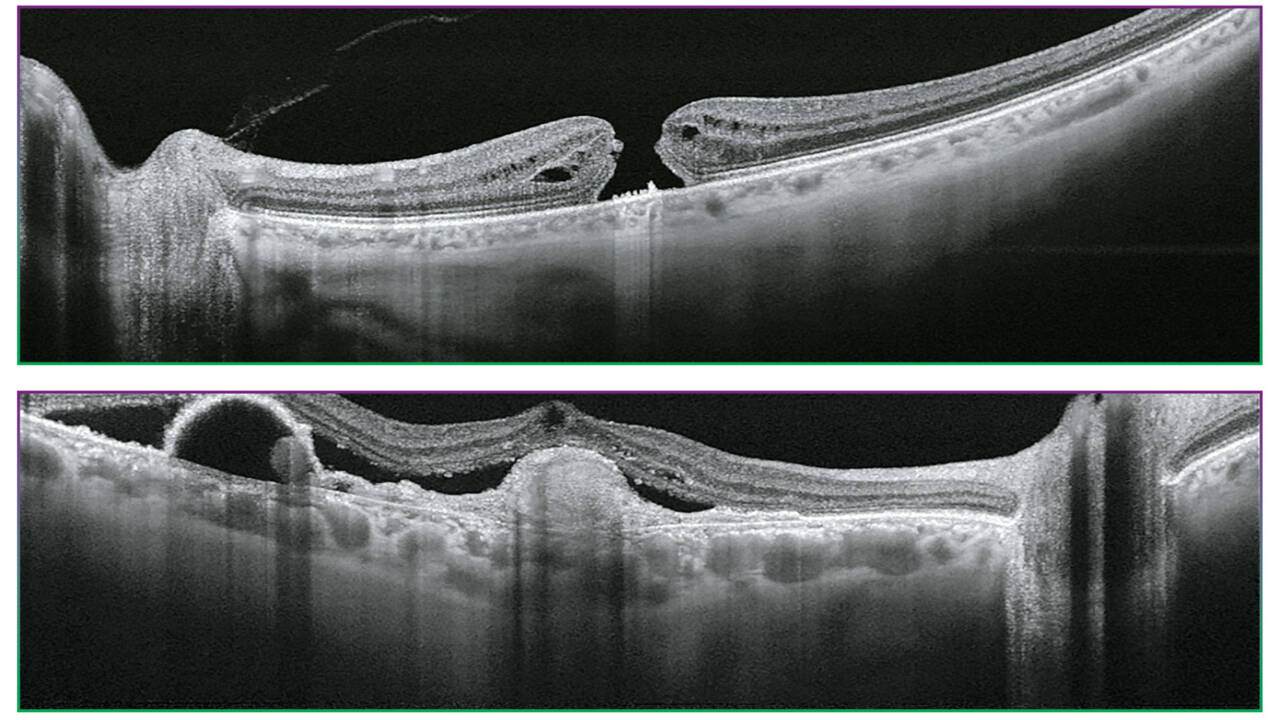

Triton’un 100 kHz tarama hızı ve 1.050 nm dalga boyuna sahip Swept Source OCT teknolojisi, kısa görüntü alma süresiyle gözün en derin katmanları için bile net ve ayrıntılı görüntüler sağlar. Sadece retina ve vitreus değil, koroid ve sklera da görüntülenebilir2.

Courtesy: Professor Jose Maria Ruiz Moreno MD, University of Albacete, Spain

Daha uzun dalga boylu ışık, dokuya daha iyi nüfuz ederek gözün en derin katmanlarının görüntülenmesini sağlar2.

100.000 A-tarama/sn’lik hızlı tarama hızı, belirli bir görüntü alma süresi içinde daha fazla A-tarama elde ederek net B-tarama’larin yakalanmasını sağlar. Bu, sakadlar ve göz kırpmaları gibi istemsiz göz hareketlerinden kaynaklanan artefaktları azaltmaya yardımcı olur.